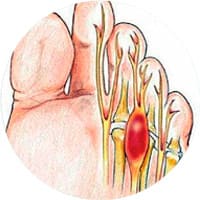

Neuroma de Morton